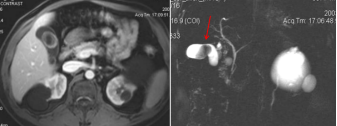

4胆管癌CT/MRI影像表现肝门胆管癌:多可在肝门区发现软组织结节或肿块,肝内胆管扩张中段和下段胆管癌:肝内和近段胆管扩张明显,胆管扩张突然变小或中断,局部胆管壁增厚或可见软组织结节或肿块,增强扫描明显不均匀强化

5胆道梗阻诊断影像学表现:一旦显示肝内胆管,提示肝内胆管扩张,显示为由肝门至外围呈树枝状分布的条状水样低密度区;肝总管和胆总管直径>1cm提示扩张存在显示为肝门或胆总管走行区的圆形水样密度影。

截屏2022-10-06 18.50.00截屏2022-10-06 18.50.22

胆道梗阻病因诊断分析良性:胆管扩张程度较轻,呈枯枝状或残根状;扩张的肝外胆管逐渐变细;扩张的胆管远端可见结石影,出现半月征靶征。恶性:胆管扩张程度较重,呈软藤状;扩张的胆管突然中断,又未见结石影;梗阻端出现软组织块影,胆管不规则狭窄;肝门部梗阻多为恶性;胰头部同时显示扩张的胆管和胰管,出现所谓双管征

胰腺癌MRI表现:横断面所见与CT相同。T1WI肿瘤呈低或等信号,T2WI肿瘤呈稍高信号;MRCP能清晰显示梗阻扩张的胰管和胆管。

截屏2022-10-06 18.59.46